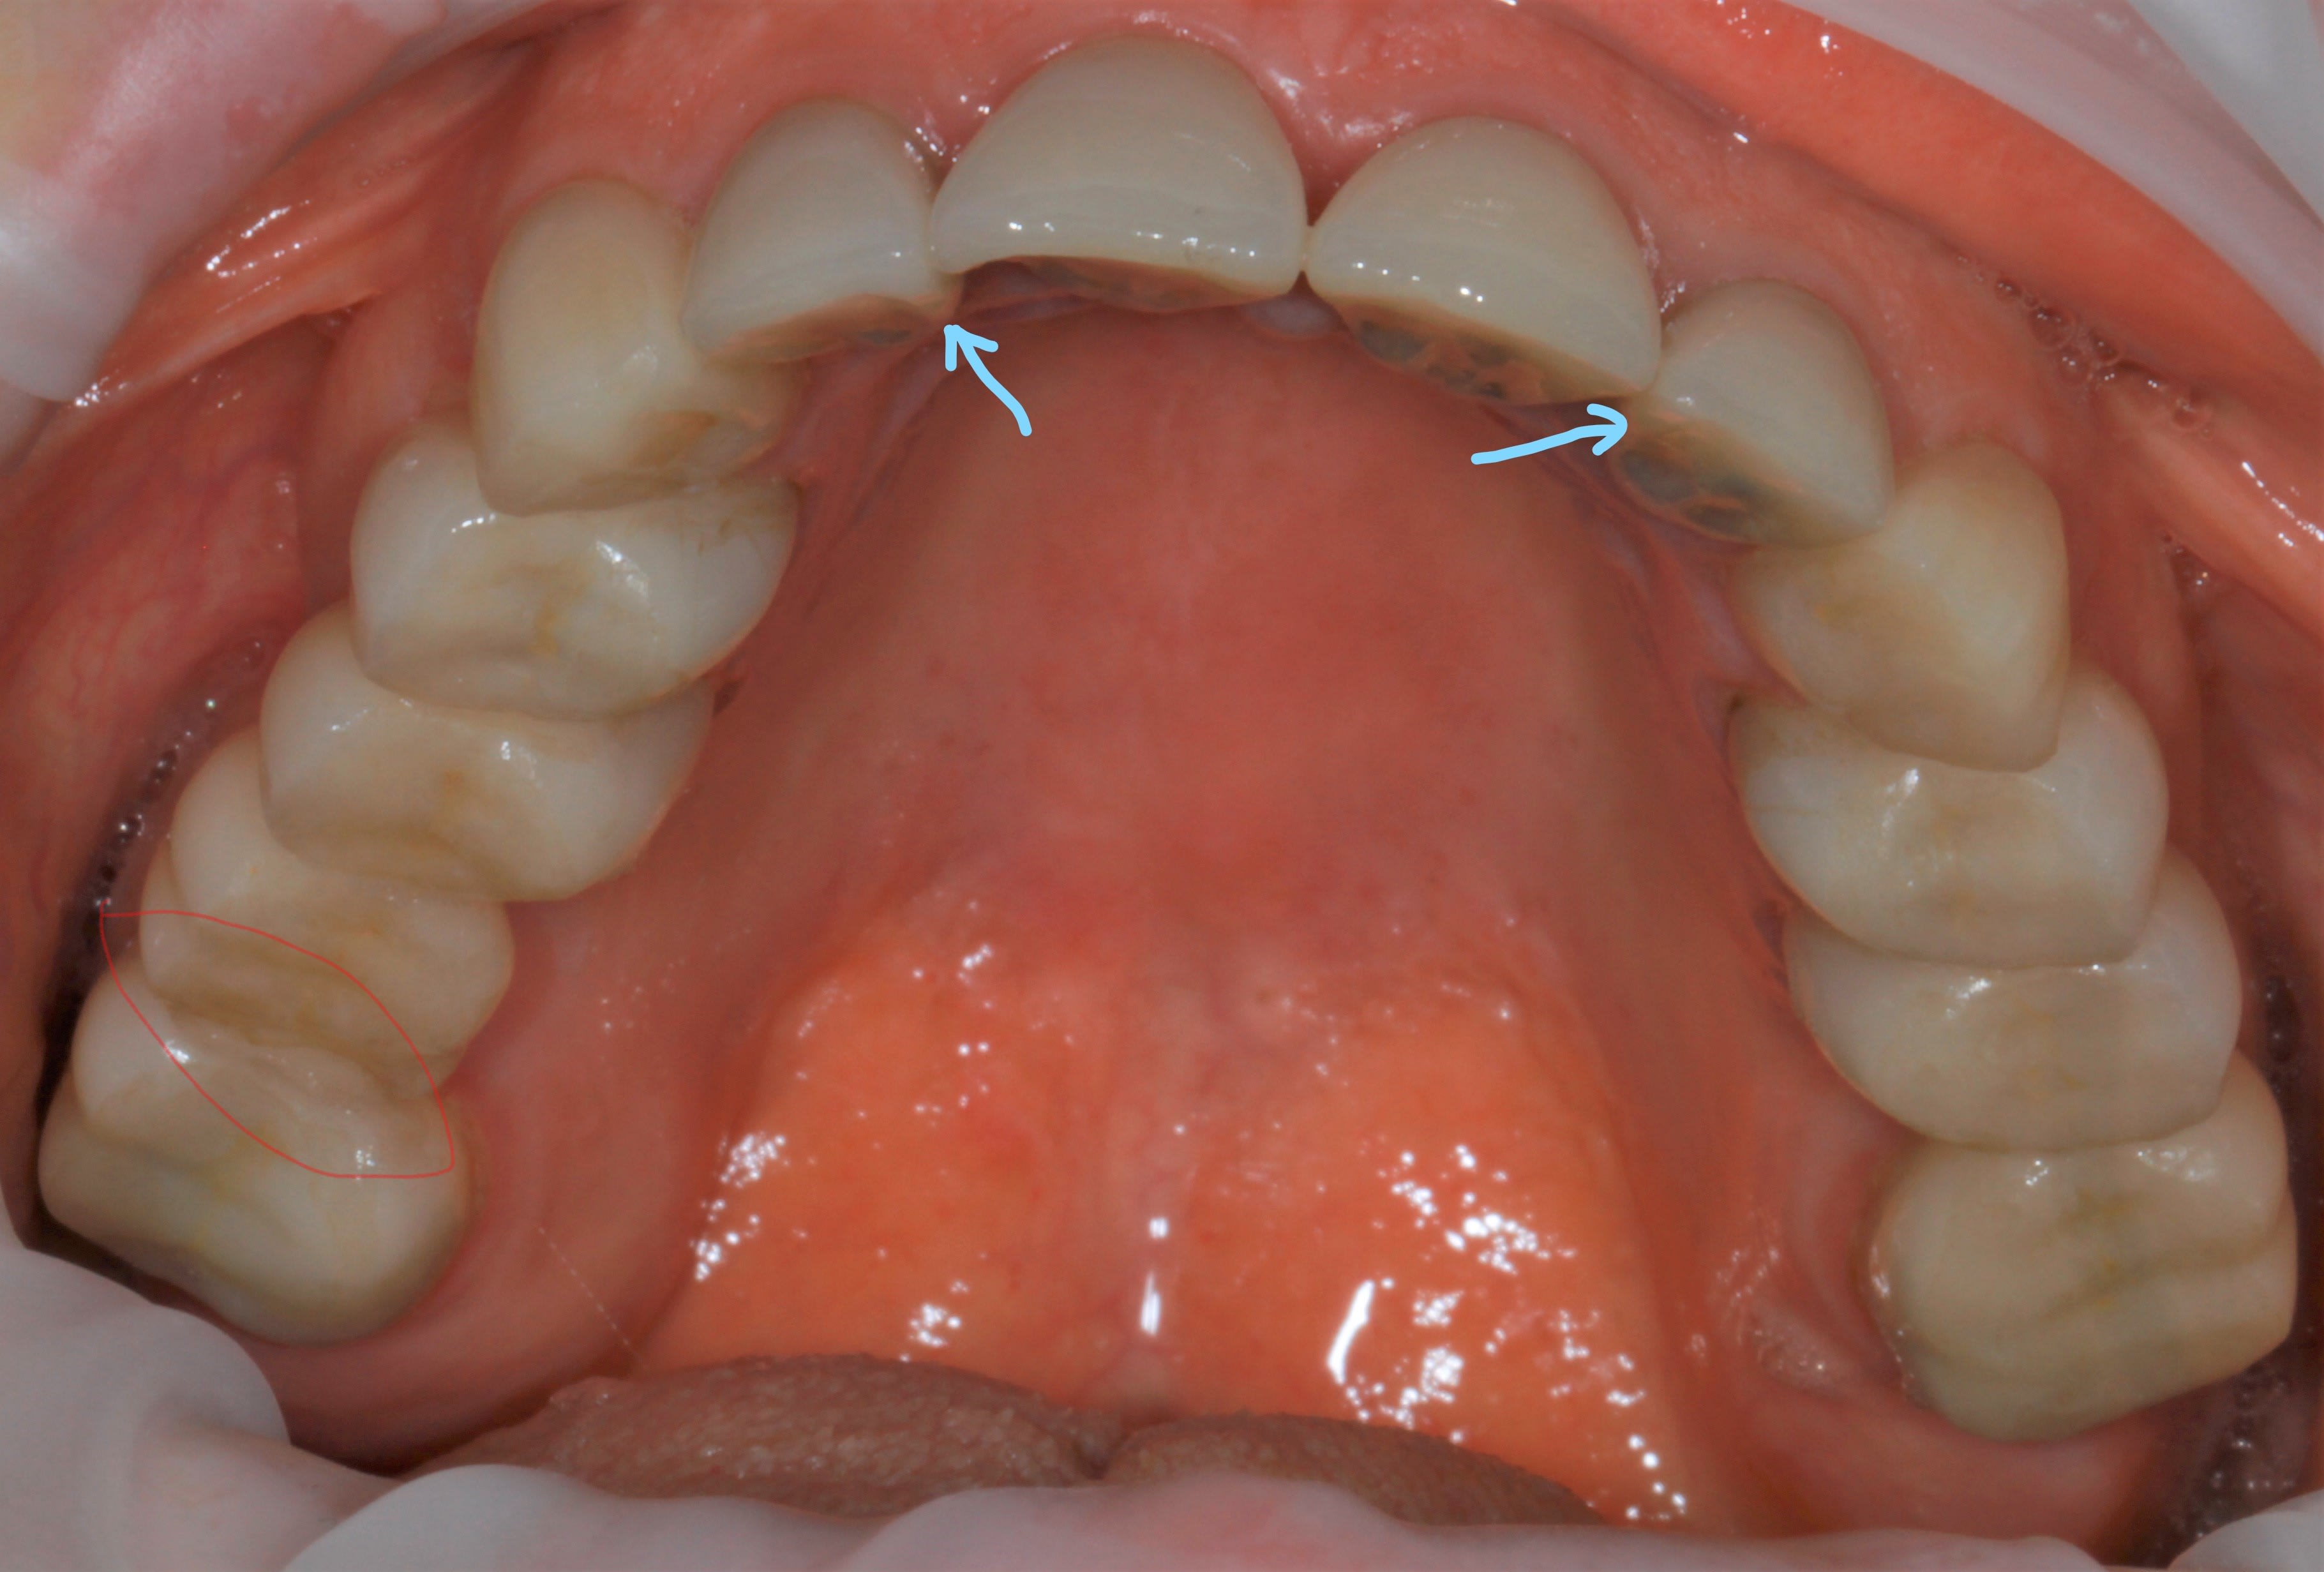

et entre 16 et 17 , alors ? on ne change tjs rien , on ne touche à rien ? , devant ?

Inkedinkedimg 8750 ilxrru li att2sr - Eugenol

ben oui ç était prévisible , à cause des 2 flèches bleues plus haut .

ç est un grand classique ça . quand tu ne peux pas être libre devant , tu t énerves derrière .

et ç est meme pas derriere en fait , mais plutôt dans une zone la plus éloignée possible de devant .

donc ç est derrière et de coté . en diagonale , quoi .

il s avère qu en plus là, derrière , ç est nouveau bridge , donc pas encore usé à sa convenance , tout au moins en latéral .

alors elle s engatse dessus avec beaucoup de force puisque ç est tout pres de l axe charniere .

là où ç est vicieux , ç est que si ton bridge etait pipé avec une grosse erreur occlusale , ben il serait tjs là , entier .

il serait tjs là , pcq si l erreur était plus importante à l arrière ,sur un bridge à la con , elle aurait eu mal soit a l atm soit aux dents antagonistes , et elle aurait cherché un autre endroit pour aller se désénerver . en l occurrence elle t aurait fracassé le bloc ant .

alors maintenant que tu a résolu le pb post ( qui n était qu une conséquence de devant ) méfies , par sympathie pour toi , je te conseillerais de vite vite retoucher au niveau des 2 flèches bleues .

si tu ne le fais pas , tu vas encore dire que je suis un chat noir , un enlaystradamus :-))))